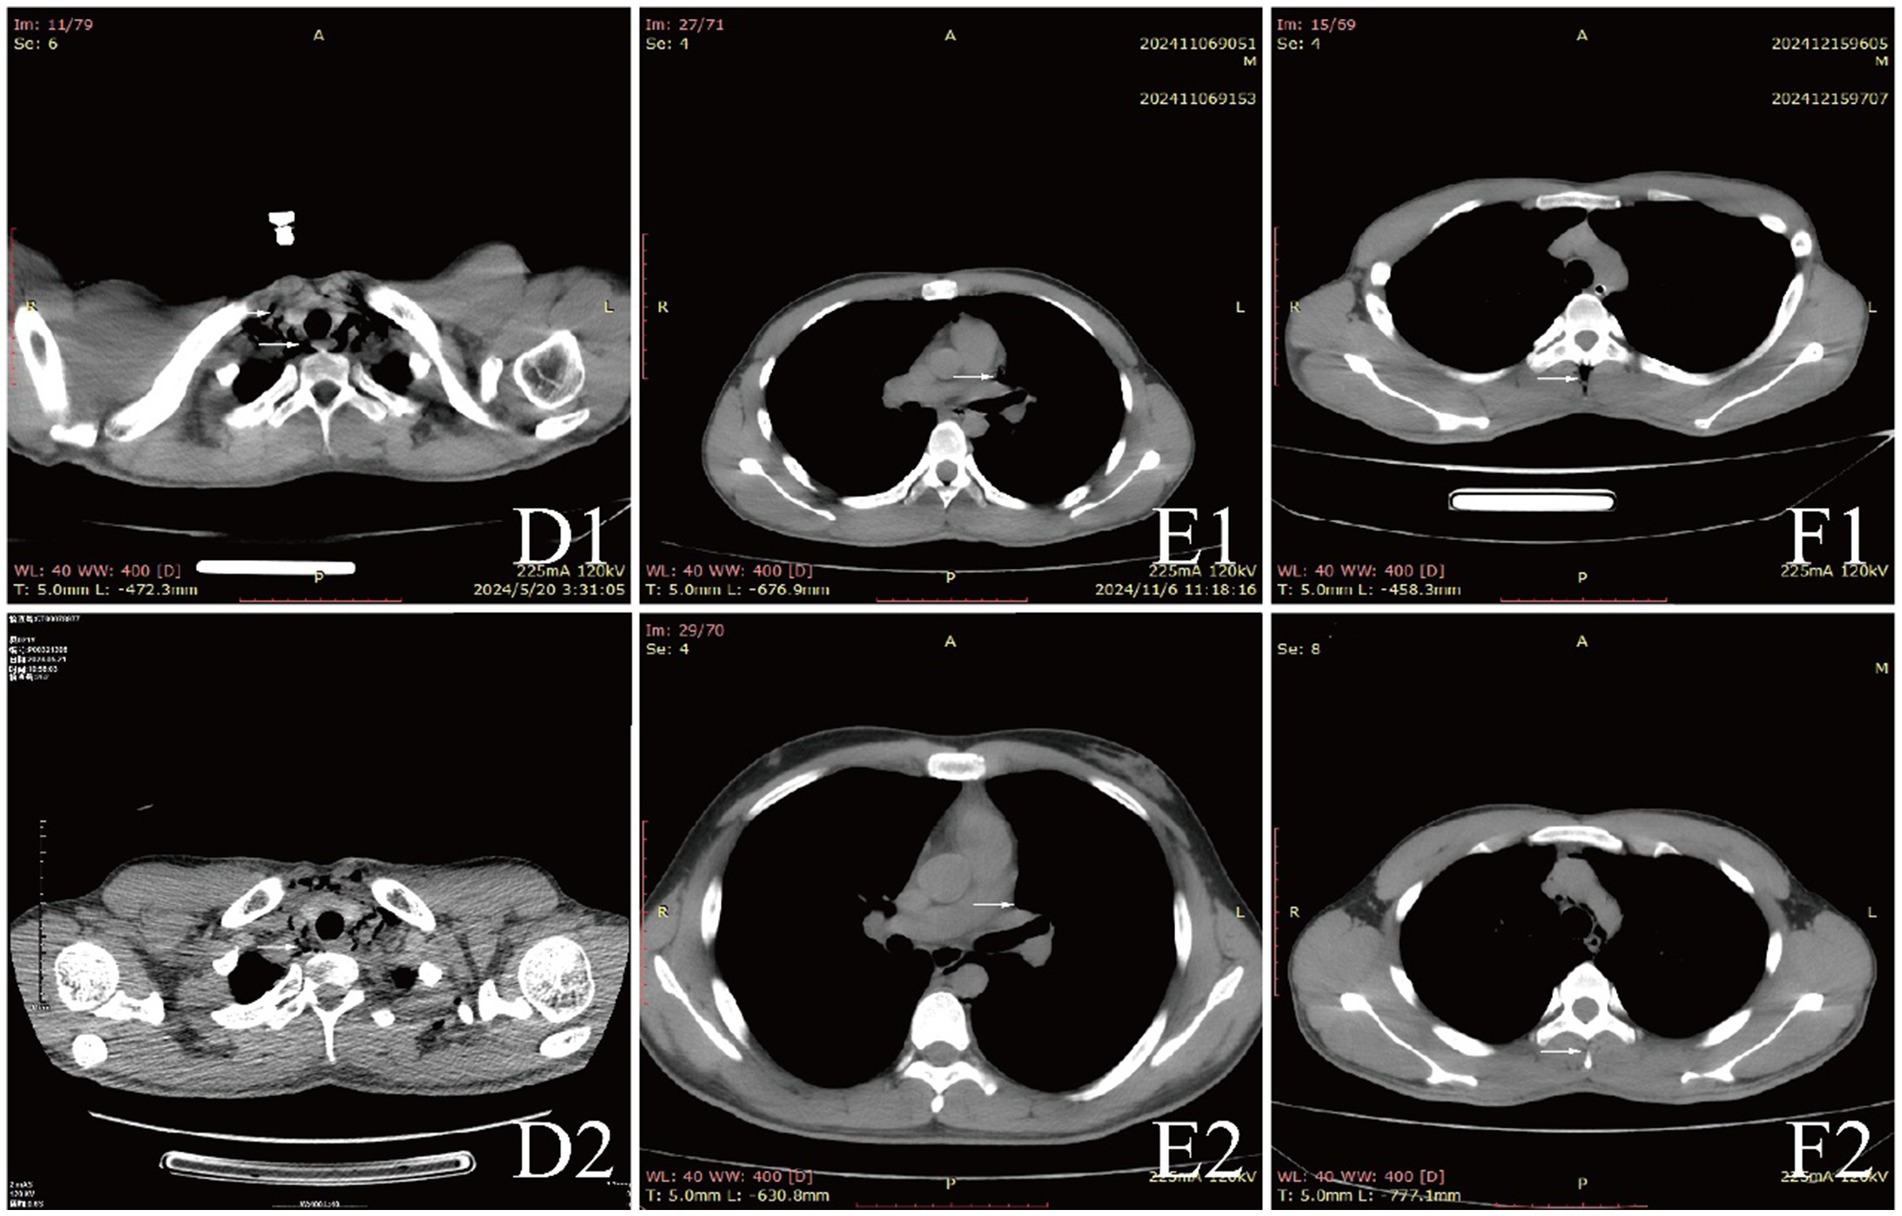

Examinations affected by the hypoxic environment of high altitudes, all patients exhibited varying degrees of increased red blood cell count, hemoglobin concentration, and uric acid (UA). Case 6 and 7, who were diagnosed with acute appendicitis and pulmonary infection, respectively, showed increased percentages of neutrophils. Case 1, in the acute phase of aortic dissection, also had an elevated white blood cell count. Additionally, we observed that D-dimer in the blood is a good indicator of myocardial or vascular damage. It showed varying degrees of elevation in patients with aortic dissection, while this indicator remained normal in other patients, maintaining a high negative predictive value. It is noteworthy that the serum potassium (K+) levels of all patients were high, with five patients having levels above the normal range. The average serum K+ level for all patients was 5.39 ± 0.73 mmol/L, this may be due to the increased metabolism in high altitude areas (Table 3). The diagnosis of extra-pulmonary emphysema for all patients was confirmed through CT examination. Case 1, 2, 3, 6, and 7 showed subcutaneous emphysema, while the others showed mediastinal emphysema. Specific imaging manifestations are shown in Figure 1.

Figure 2. CT comparison images of extra-pulmonary emphysema treatment before and after for Case 4 to Case 6.

All patients were diagnosed with extra-pulmonary emphysema through CT scans, which showed gas infiltration in the mediastinum or subcutaneous tissue. The patient with aortic dissection was urgently transferred to a lower altitude area for “aortic arch artificial vessel replacement surgery.” Case 6 underwent “appendectomy” for treatment, and three patients received antibiotic therapy. All patients were given symptomatic and supportive treatment, including oxygen therapy. Six were given oxygen via a face mask, two received a nasal cannula, and one was assisted with non-invasive ventilation. In addition to case 1, they also received hyperbaric oxygen therapy at 2.0 ATA. Follow-up showed that all patients responded well to the treatment, their conditions improved, and the emphysema was largely absorbed (Figures 1–3).